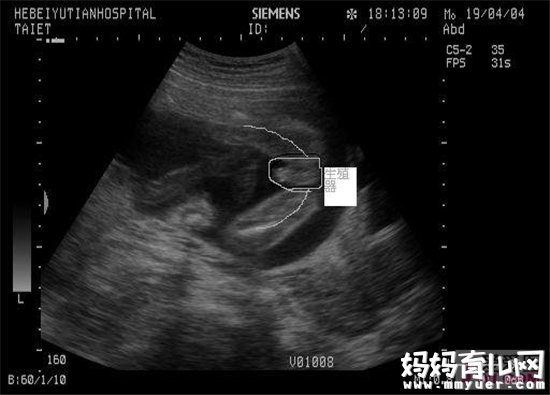

科学预测方法一:B超检查

虽然由于技术的改善,B超现在已经是一种判断生男生女的相当准确的方法。虽然生男生女在怀孕大约18周时就能检查出来,但在你做B超的时候,宝宝可能会朝着相反的方向或双腿交叉,医生无法看见他(她)的生殖器部位。

你需要知道的是,在中国,如果没有明确的医学需要,通过B超检查确定生男生女是被明确禁止的。而且B超检查的确也会出现错误,少数人还可能会因为知道了生男生女而选择终止怀孕。因此,医院不会告诉准父母们宝宝的性别。